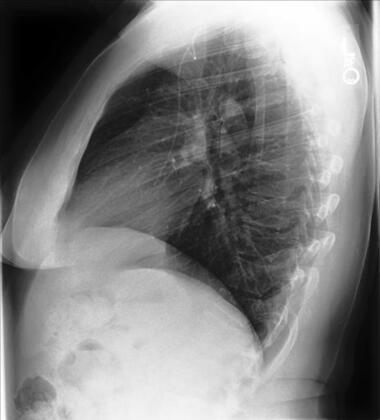

Chest X-rays may be divided into three principal types, according to the position and orientation of the patient relative to the X-ray source and detector panel: posteroanterior, anteroposterior, lateral. The posteroanterior (PA) and anteroposterior (AP) views are both considered as frontal, with the X-ray source positioned to the rear or front of the patient respectively. The AP image is typically acquired from patients in the supine position, while the patient is usually standing erect for the PA image acquisition. The lateral image is usually acquired in combination with a PA image, and projects the X-ray from one side of the patient to the other, typically from right to left. Examples of these image types are depicted in Figure 1.

Figure 1: Left: posterior-anterior (PA) view frontal chest radiograph. Middle: lateral chest radiograph. Right: Anterior-posterior (AP) view chest radiograph. All three CXRs are taken from the CheXpert dataset [131], patient 184.